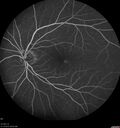

64 year old man. Diagnosed with hemangioma in 2015. PDT in 2016. Images are from 2020 when fluid started to reaccumulate. Needed PDT repeated two more times. PDT treatments: [1] 2/19/2015 -  Pavan (IOP  problem after PDT)  AND [2] 11/2/21 PDT (7 mm temporal to fovea) - SMC  AND [3] 7/22/22 PDT 7.5 mm Temporal to the fovea

Choroidal Hemangioma Requiring PDT repeatedly210 views64 year old man. Diagnosed with hemangioma in 2015. PDT in 2016. Images are from 2020 when fluid started to reaccumulate. Needed PDT repeated two more times.

PDT treatments: [1] 2/19/2015 -  Pavan (IOP  problem after PDT)  AND [2] 11/2/21 PDT (7 mm temporal to fovea) - SMC  AND [3] 7/22/22 PDT 7.5 mm Temporal to the fovea